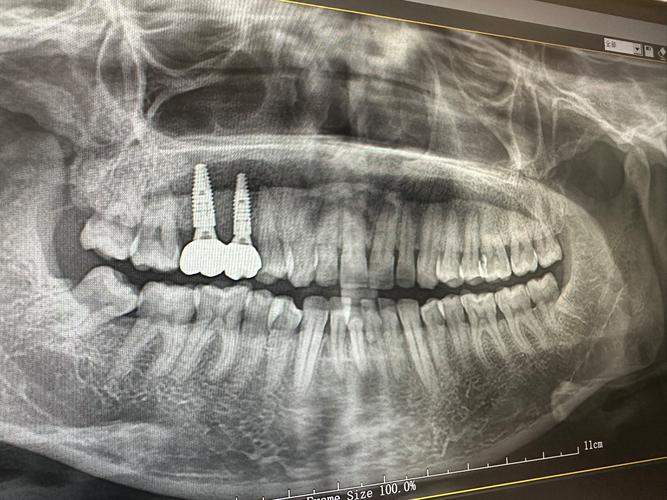

- 术前检查与评估:通过口腔CT、全景片等检查,评估牙槽骨密度、高度及宽度,判断是否需要植骨(如骨量不足,需先行植骨手术,3-6个月后再行种植);同时排查高血压、糖尿病等全身性疾病,确保符合手术条件。

- 种植体植入:在局部麻醉下,通过微创手术将奥齿泰种植体植入牙槽骨,过程约30分钟-1小时,创伤小、疼痛感轻(多数患者反馈类似拔牙)。

- 骨结合与二期手术:种植体植入后需等待骨结合(3-6个月),期间避免种植体受力;骨结合完成后,进行二期手术安装基台(暴露种植体顶端),约2周后取模制作牙冠。

- 牙冠佩戴与复查:牙冠制作完成后(通常1-2周),试戴调整并固定,完成修复;术后1周、1个月、6个月定期复查,监测骨结合情况及种植体稳定性。